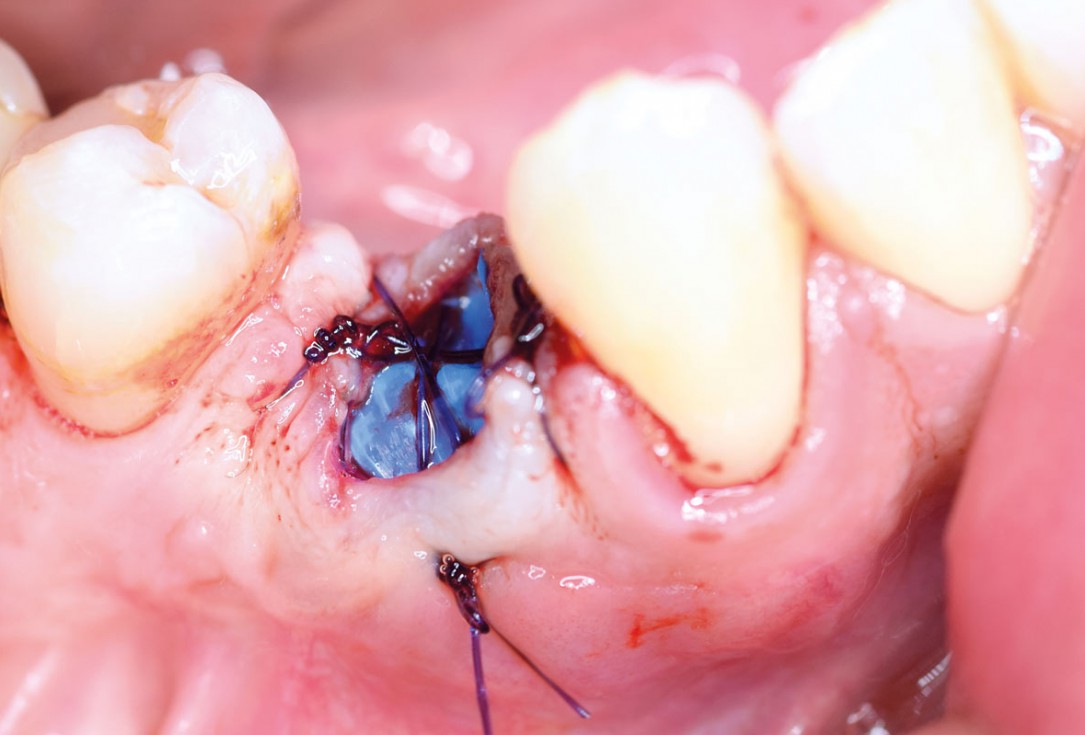

Full bone regeneration in extraction socket augmented with maxgraft® and Jason® membrane – Dr. C. Landsberg